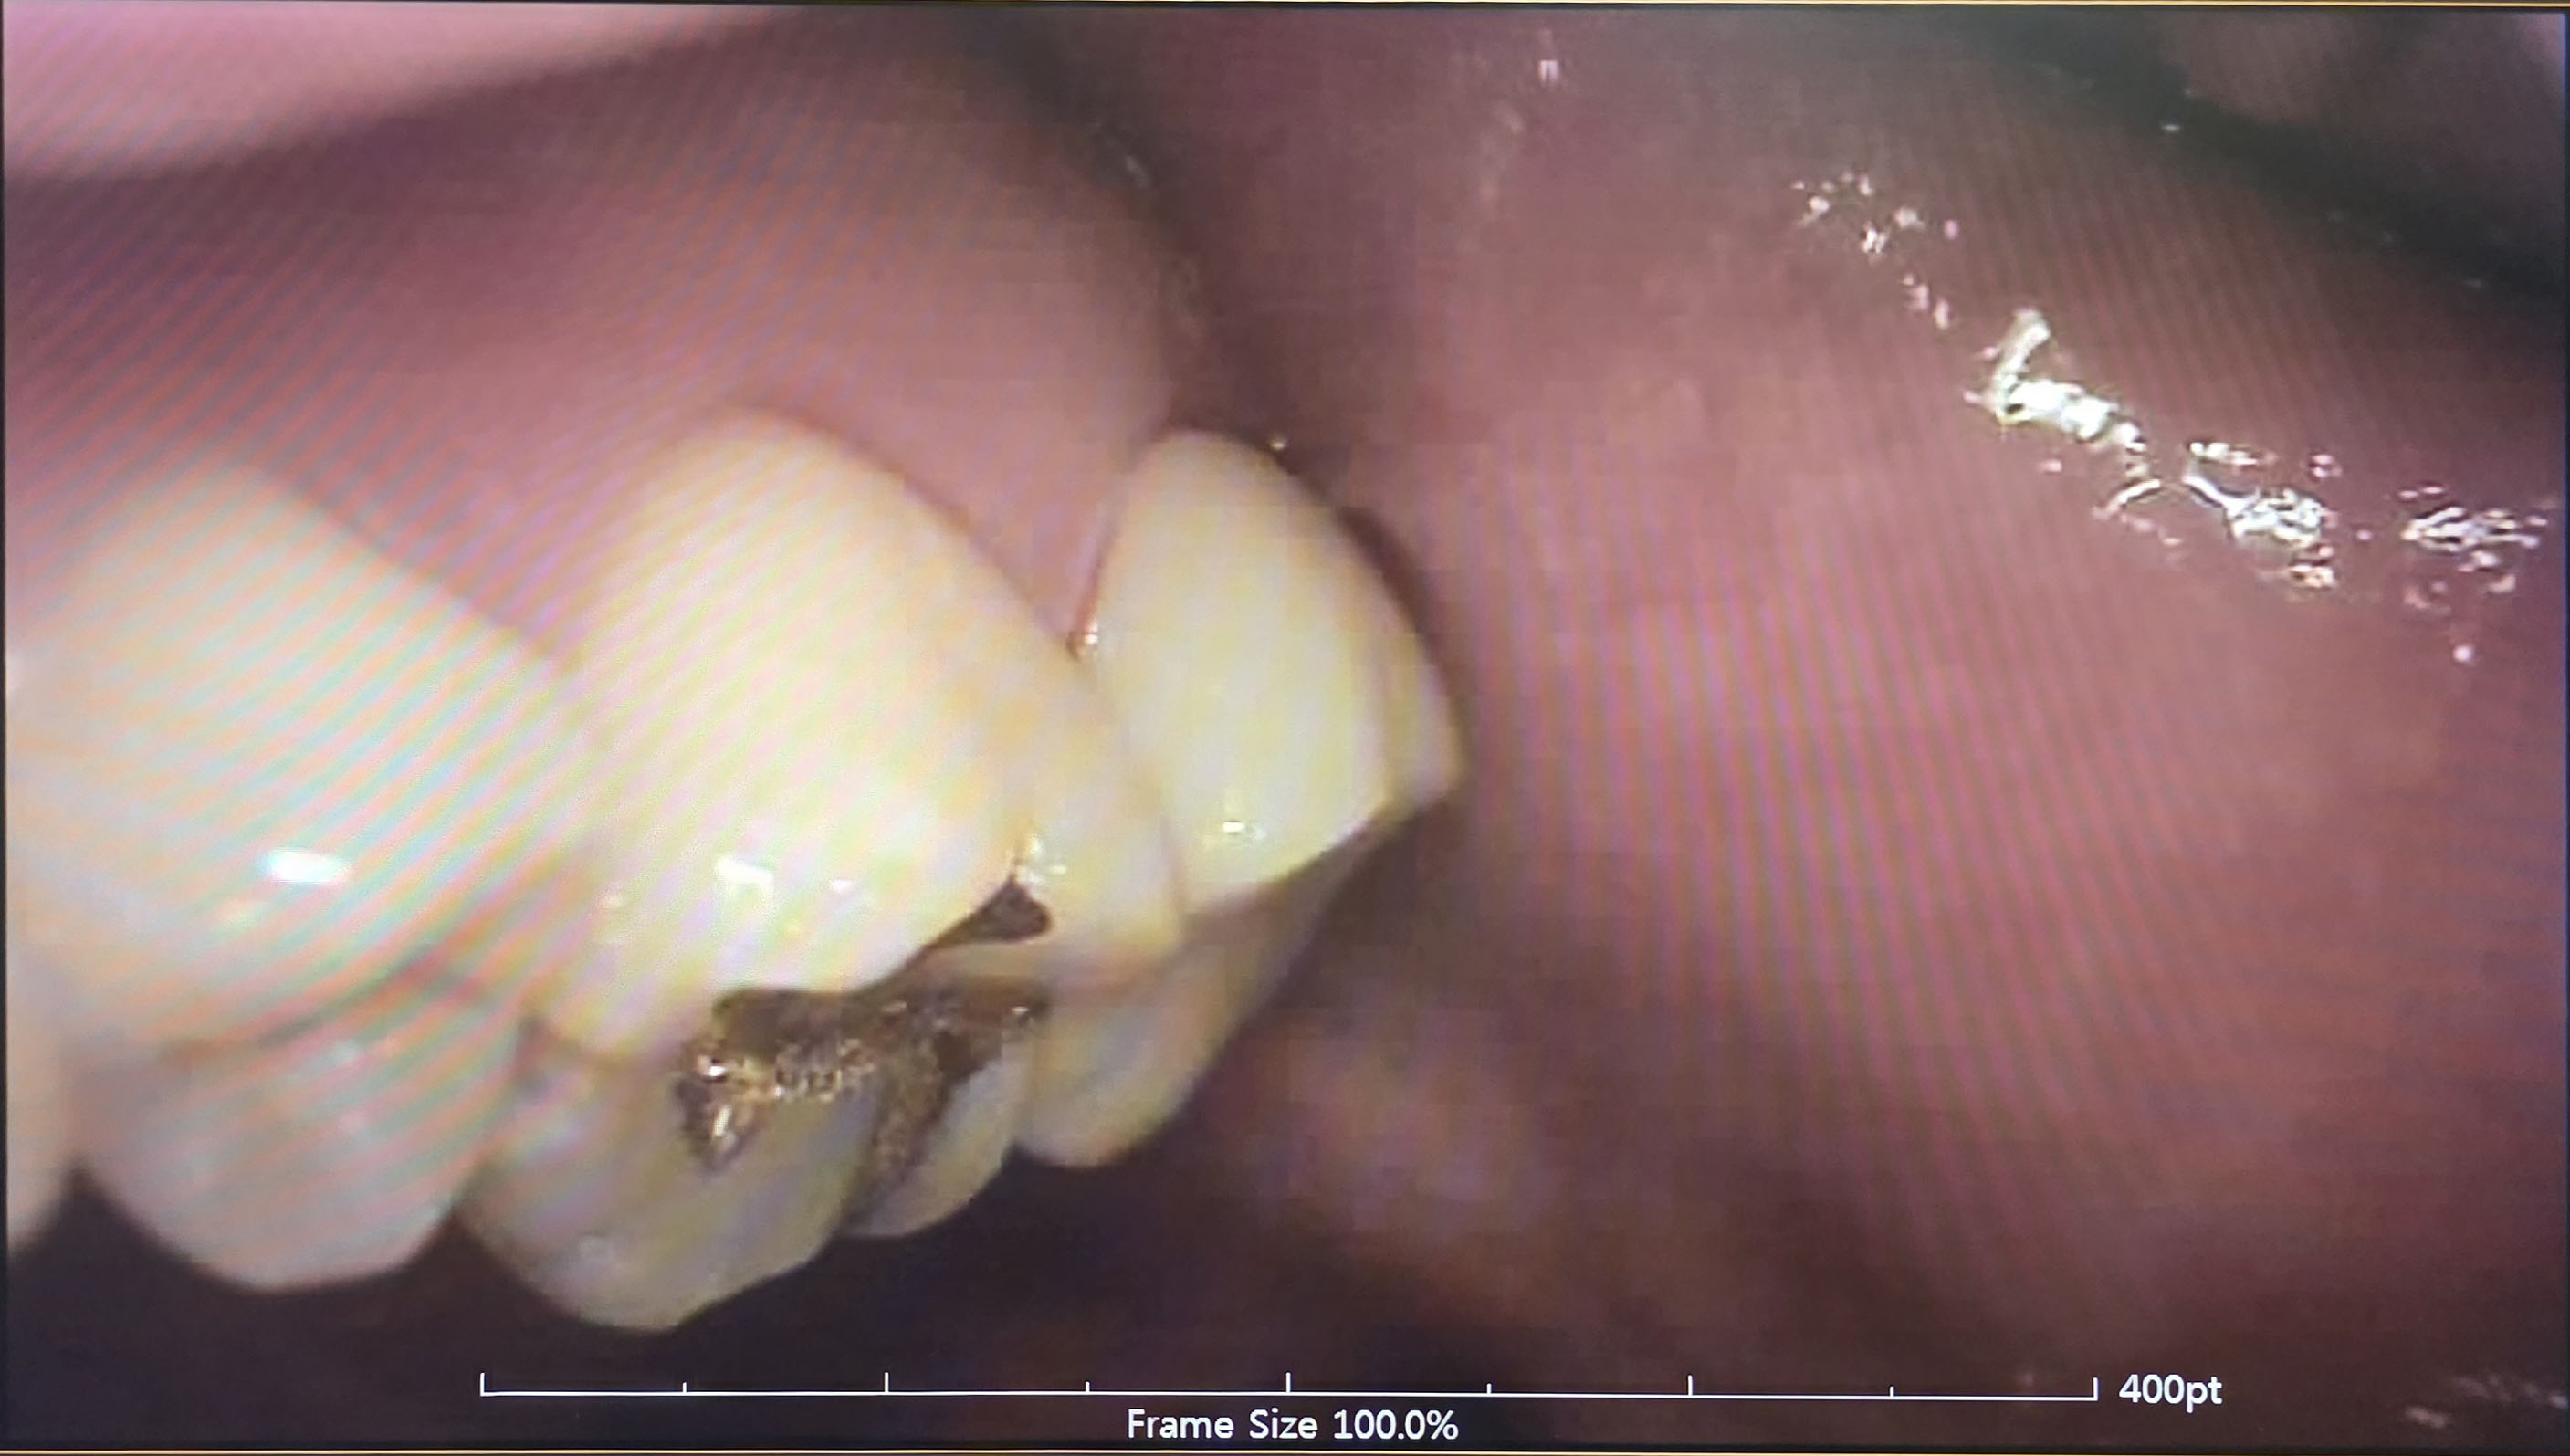

본뜨기 전에 직전에 치아를 갈아내는데 어떤 모양인지 궁금해서 사진을 한 장 찍었습니다. ㅎㅎ

치아는 아주 잘 나왔다고 합니다.

흰색일 줄 알았는데 생각보다 누런색이라 놀랐네요!

그런데 씌우고 나면 감쪽같다고 합니다.

내치아가 이렇게 누런색이었다니..... ㅡ,.ㅡ;;